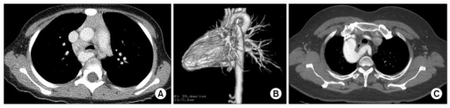

a-c)Preoperative computed tomograms of vascular rings

Infants with vascular rings typically present before 12 months with respiratory or esophageal symptoms like stridor, wheezing, cough, dysphagia, or difficulty feeding. The stridor improves with neck extension, differentiating from laryngomalacia which is relieved by prone or upright positioning, and will not be relieved with corticosteroids or epinephrine, unlike croup. Diagnosis requires a high degree of clinical suspicion and can be confirmed with barium contrast esophagogram for those with esophageal symptoms, bronchoscopy, or CT or MRI.[3]